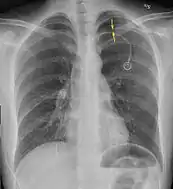

| A large right-sided spontaneous pneumothorax (left in the image). An arrow indicates the edge of the collapsed lung | |